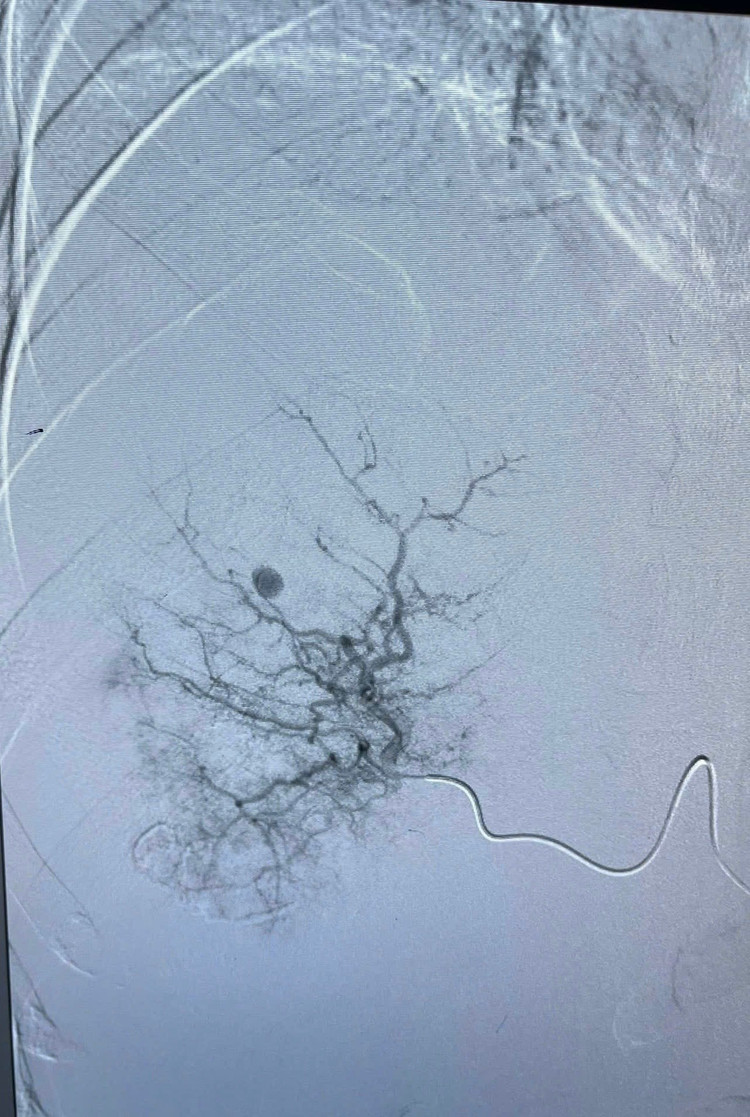

Bệnh nhân T.V.L 46 tuổi, huyện Quỳnh Lưu, tỉnh Nghệ An, nhập viện trong tình trạng mệt mỏi, đau bụng vùng quanh rốn và hạ sườn phải, bụng chướng căng. Kết quả chụp CT Scanner và MR ổ bụng cho thấy hình ảnh tổn thương gan Phải hướng đến áp xe gan đã vỡ, chảy máu trong ổ bụng lượng nhiều.

Hình ảnh ổ áp xe vỡ trên phim chụp CT - Ảnh BVCC

Trong quá trình can thiệp, các bác sĩ phát hiện ổ áp xe gan vỡ kích thước 57,6mm x 40,6mm, có nhiều ổ giả phình, nhiều dịch máu và mủ tràn ổ bụng. Sau can thiệp, tình trạng bệnh nhân ổn định, dấu hiệu sinh tồn tốt.